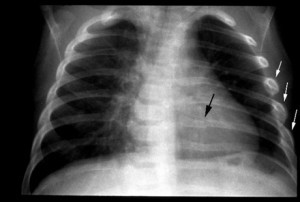

Чаще выявление травмы грудного каркаса у находящего в сознании пациента не является проблемой. Аускультация и пальпация дают возможность предположить наличие перелома. Для подтверждения диагноза требуется ряд обследований.

Инструментальные методы диагностики:

- обзорная рентгенография грудной клетки;

- рентгеноскопия легких;

- УЗИ плевральной полости;

- КТ и/или МРТ грудной клетки;

- плевральная пункция.